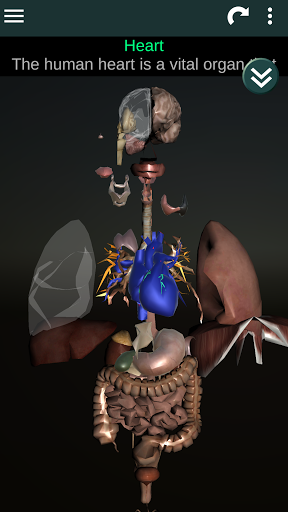

Internal Organs in 3D Anatomy لـ Vodafone Smart N9 Lite

(الأجهزة الداخلية في)

Internal Organs 3D Anatomy 3.4

يمكنك هنا تنزيل ملف حزمة تطبيق أندرويد "Internal Organs 3D Anatomy" الخاصة بجهازVodafone Smart N9 Lite مجانًا، نسخة ملف حزمة تطبيق أندرويد - 3.4 للتحميل على Vodafone Smart N9 Lite اضغط ببساطة على هذا الزر. إنه سهل وآمن. نحن نقدم فقط ملفات حزمة تطبيق أندرويد الأصلية. إذا انتهكت أية مواد موجودة في الموقع حقوقك قم بإبلاغنا من خلال